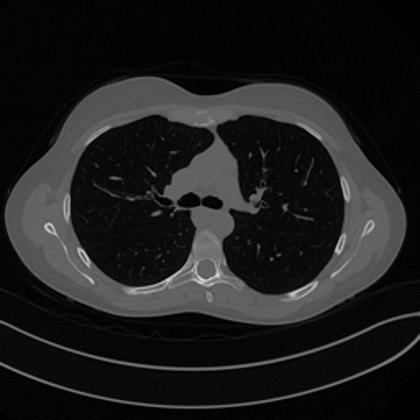

For this example we will consider an example which we will use multiple time throughout this module: the Mayo’s dataset. The Mayo’s dataset is a commonly-used dataset for benchmarking algorithms for Computed Tomography (CT) image reconstruction from sparse measurement. It can be downloaded from the following link: Mayo’s Dataset Download.

This dataset comprises a total of \(N = 3305\) training images and \(N = 327\) test images, representing the CT scan of 10 human chests.